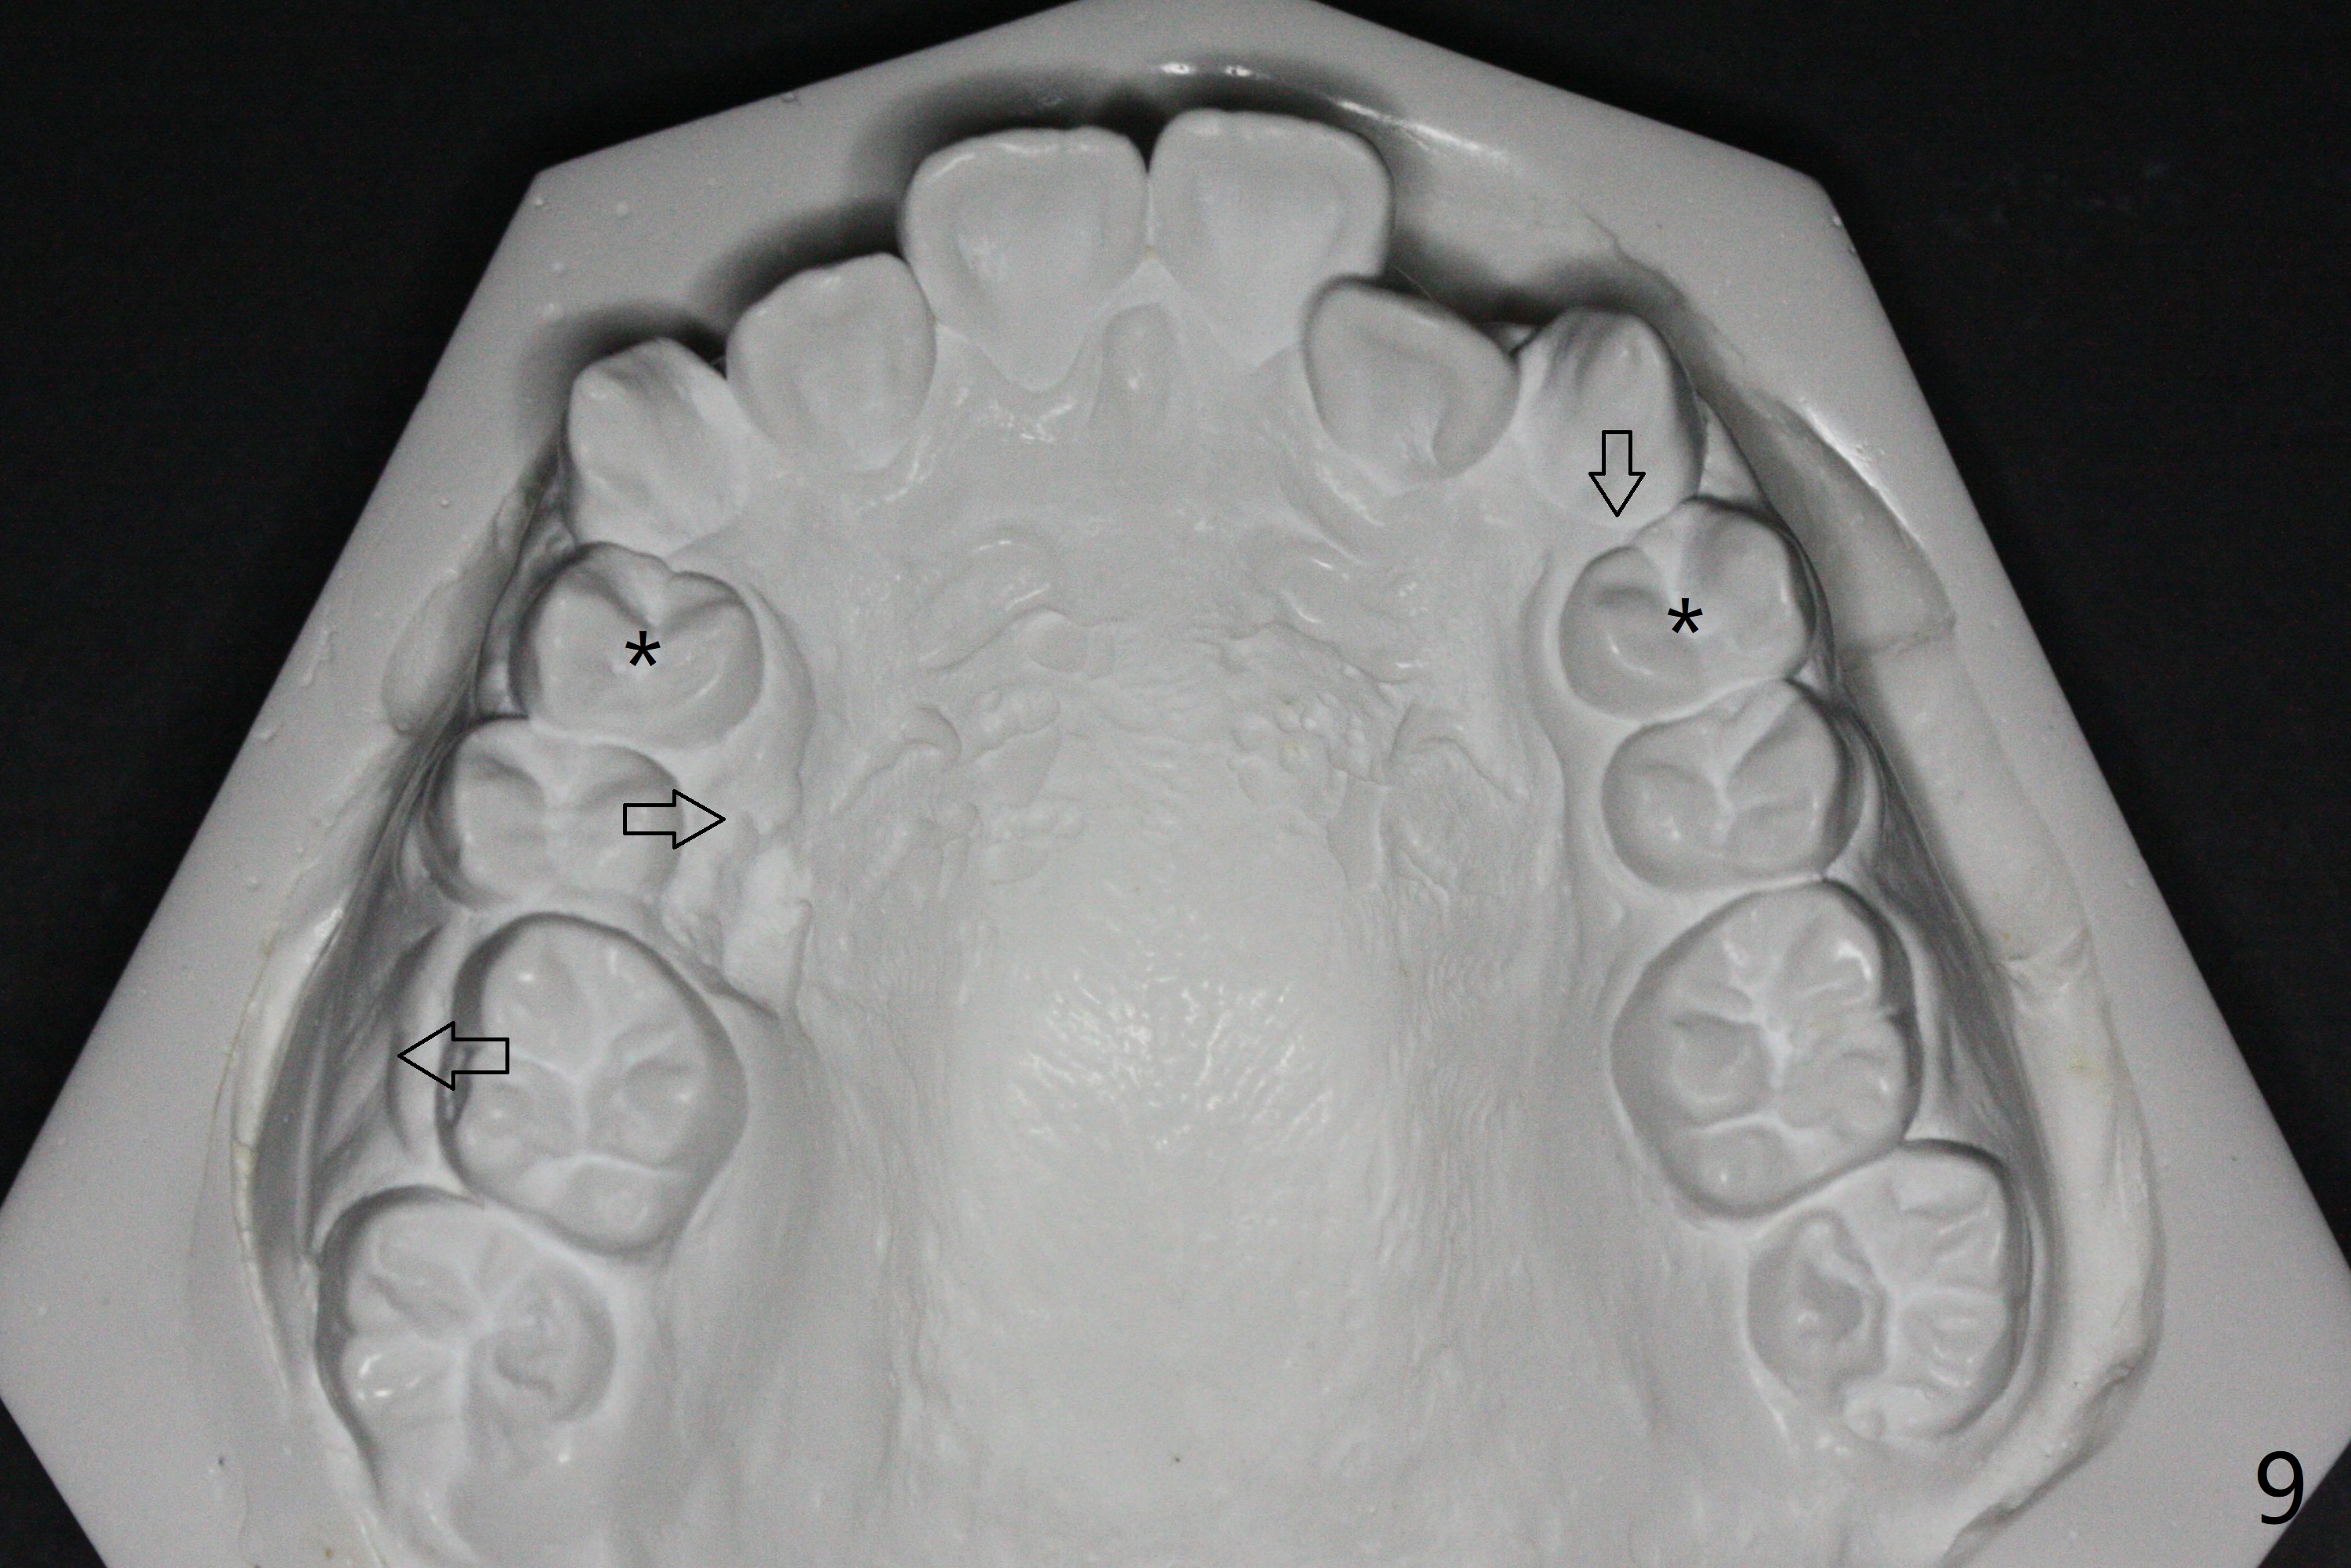

A 13-year-old man has protrusive lips (Fig.1,3,4) with upper midline deviation to the left (Fig.2).  Crowding is severe with LR5 severe lingual inclination (Fig.5,6,10).  To facilitate L6s' uprighting (Fig.10), LR5 and 3 of the 1st bicuspids will be extracted (Fig.6-8 x or *) and molar bands with lingual cleats will be used for the lower.  Cross arch molar retraction will be initiated immediately.  Open coil spring will be placed between UL1 and 3 with the 1st wires to correct the upper midline deviation and to gain the space for UL2.

The patient will return 2 months post extraction.  Shifting is expected to occur next to extraction sites (*) as indicated by arrows in Fig.9,11.  Take photos if it is the case.  Place bracket at UL2 if there is no space issue, but upside down (why?).  The most flexible wire is anticipated.  To establish Class I occlusion when wires are stiffer (18ss), LL5,6 will be mesialized as equally as LL3 distalized, while UL5,6 maintained basically in situ (Fig.11).  How to accomplish?

In fact, automatic shifting is striking.  For example, UR5 lingualization (Fig.12 arrow) makes it easy to insert 12 niti wire.  Distalization of the lower bicuspids and canine is more obvious (Fig.13,14 arrows) than the upper counterparts.  Because of incomplete eruption, it is difficult to band L7s; instead brackets are placed (Fig.15-17).  The purpose of LR one is to facilitate LR6 buccalization (Fig.15,16), whereas LL one to correct rotation of itself (Fig.17).